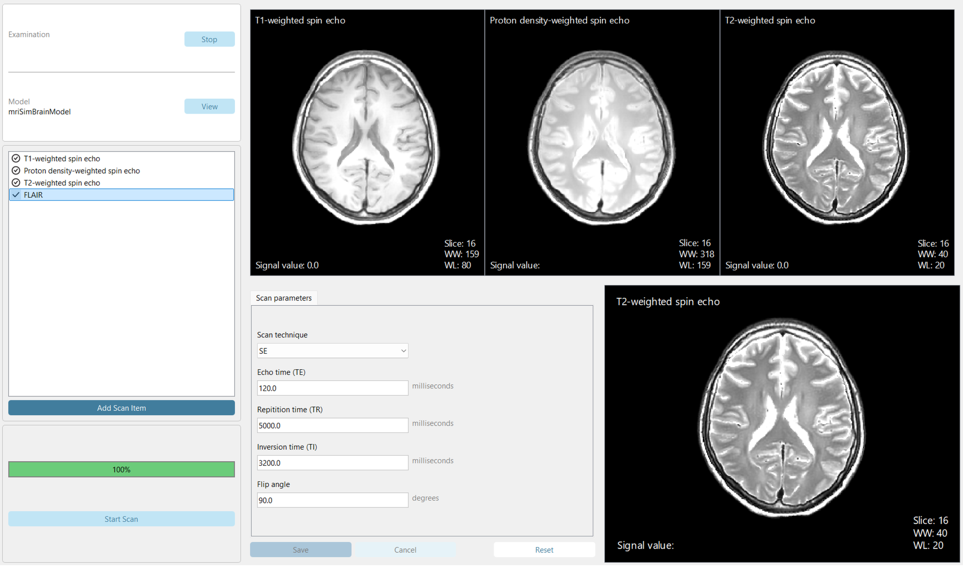

A first version of eduMRIsim has been developed which allows students to perform a simplified clinical MRI scanning workflow and experiment with various MRI settings that influence image contrast. Students can compare side-by-side images to observe how adjustments affect image quality.

To assess the first version of eduMRIsim, 20 researchers involved in MRI education as (assistant) teachers or project supervisors completed example tutorial exercises with the simulator and answered a questionnaire. For user-friendliness, 95% of participants rated eduMRIsim a 4 or 5 on the 5-point Likert scale with 1 being “not at all” and 5 being “very” (average: 4.3). Clinical similarity received an average score of 3.6. The simulator’s value for teaching the effect of scan parameters on image appearance was also rated highly, with an average of 4.5.

A second version of eduMRIsim is currently under development and will include a more clinically realistic workflow, which a group of TU/e Computer Science Bachelor students significantly contributed to during their graduation project. This version will also feature additional adjustable parameters and simulate patient motion along with other imaging artifacts to improve the realism of the generated MR images.